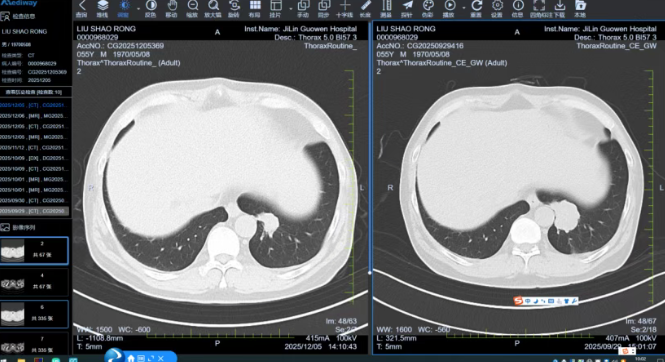

消化道肿瘤中心首席专家张晓东主任据此建议XELOX方案联合靶向药进行强化化疗,放疗科则为直肠原发灶规划精准放疗。治疗过程中,MDT团队始终保持动态跟踪。每两周期治疗后,影像科精确测量病灶变化,肿瘤内科根据反应调整方案。4周期后,评估结果令人振奋:肺部转移灶缩小,直肠原发灶明显退缩,转化治疗成功。

随即启动第二次MDT会议,焦点转向手术时机。胸外科专家评估后认为转移灶贴近主动脉,适合手术切除;胃肠外科专家则规划在肺手术后4-6周进行直肠原发灶手术。每一步时机都经由多学科共同研判,确保治疗环节无缝衔接。